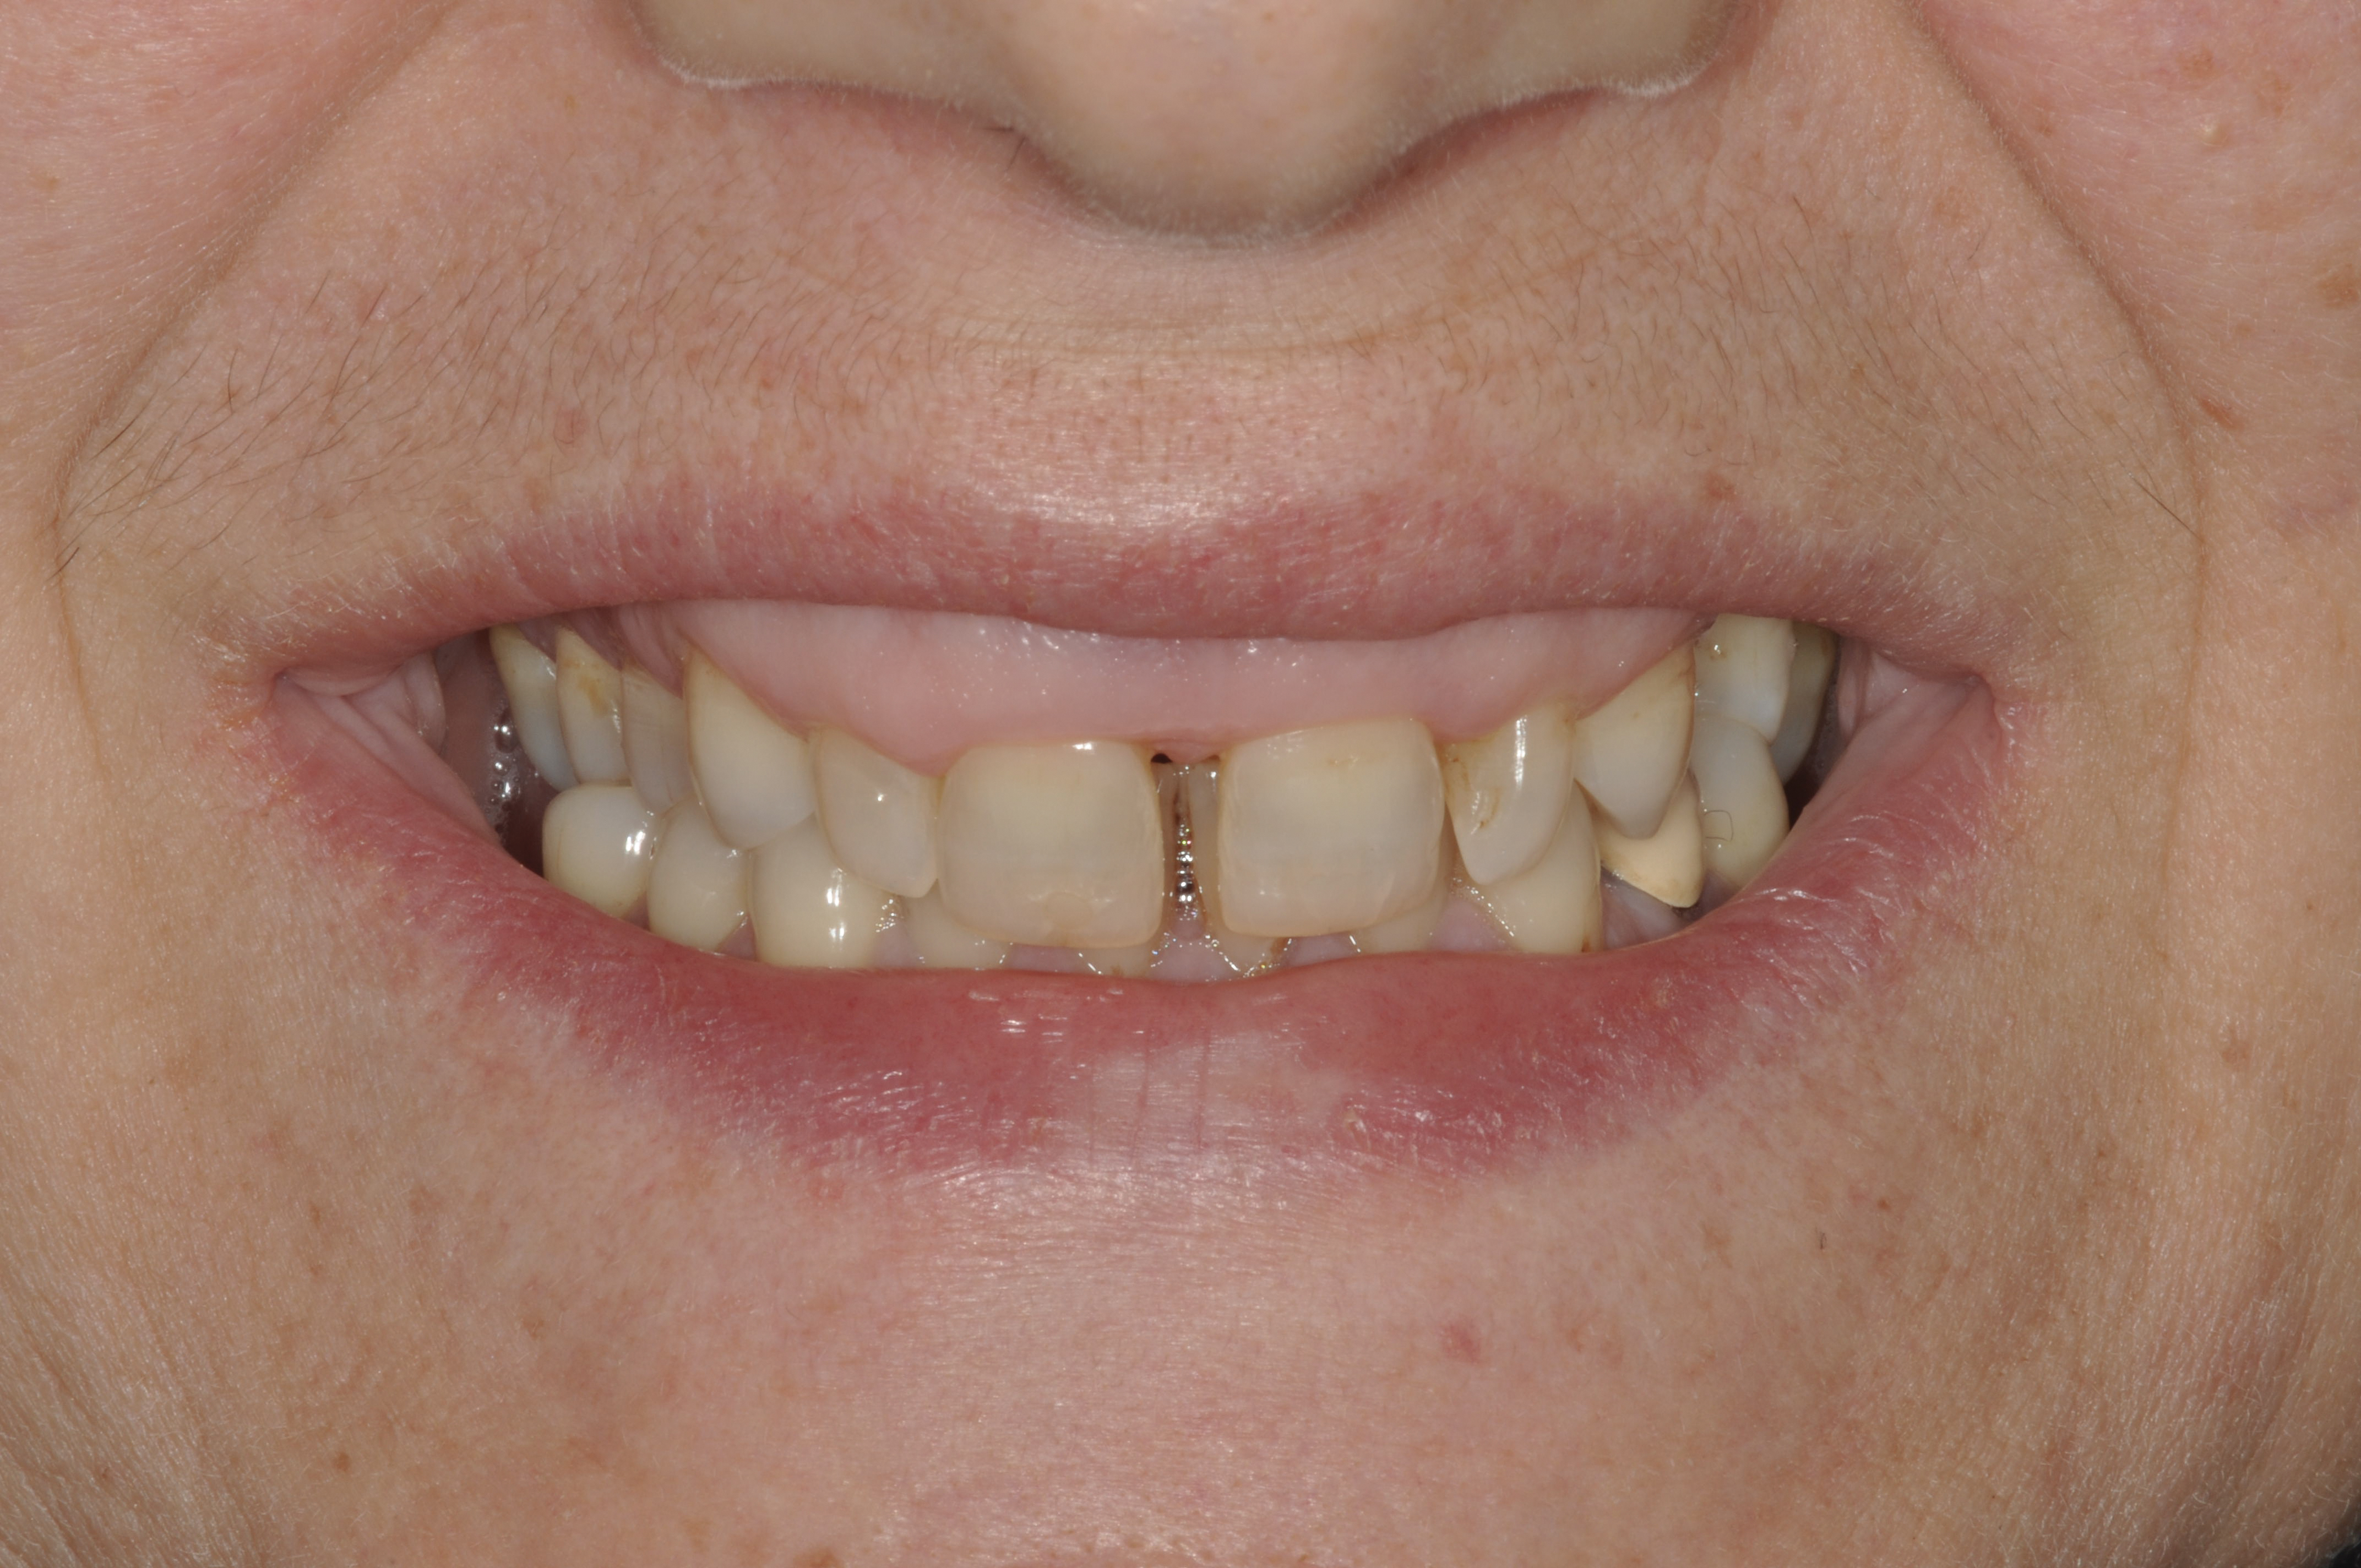

Smile line assessment is a validated process that is used for esthetic evaluation.1 Gummy smile (GS) has been defined as a nonpathological condition causing esthetic disharmony in which more than 3 mm of gingival tissue is exposed when smiling2 (Figure 1). The possible causes are excessive maxillary growth, short upper lip, or abnormal eruption of maxillary anterior teeth. Subsequently, short tooth syndrome (STS) has been defined as a condition caused either by excessive gingival display or lack of incisal tooth display during smiling or a low smile line.3

Fig 1. Patient with a gummy smile.

Figure 1